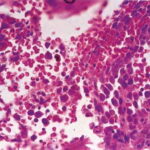

acute-myelogenous-leukemia1